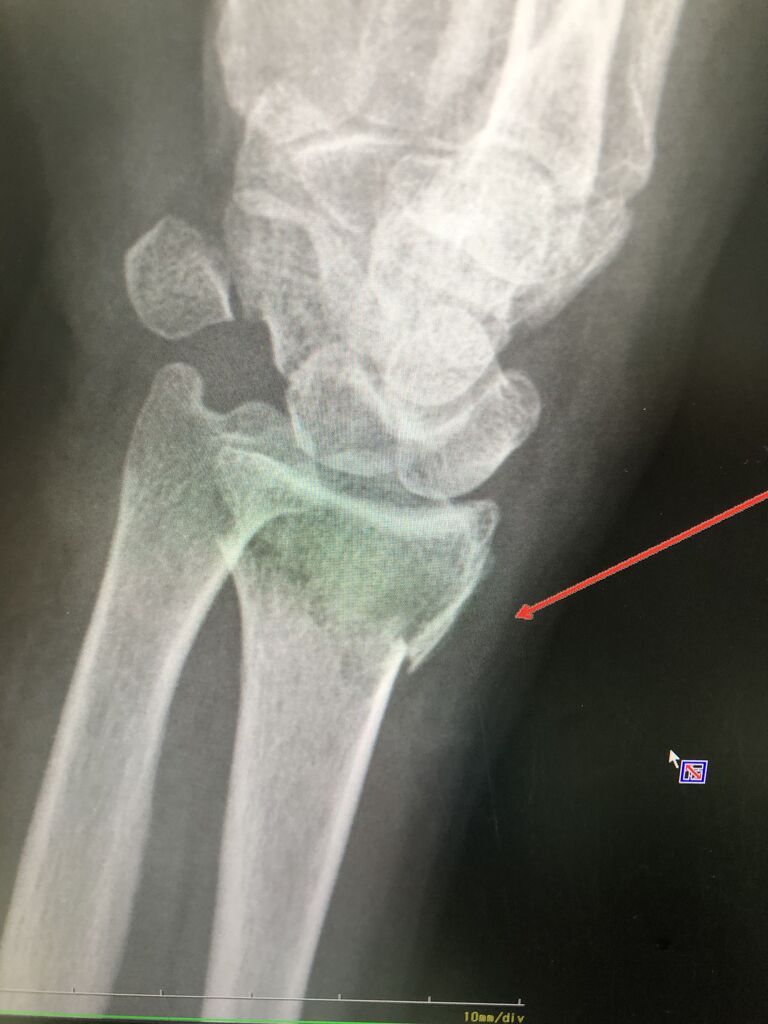

野球アスリートで多い骨折が

この 有鈎骨骨折です

レントゲンでも診断つきますが、

わかりにくいため、CTで精密検査します

ほっておくと、偽関節になり しびれ、

力が入らなくなるため、注意が必要です。

他で、診断つかず

偽関節になって来院されました

何とかスポーツ活動できているので、

本人の希望で、

手術も視野にいれ、保存的に治療していきます。